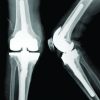

According to Beavis et al. [4] classification, the fracture was Type 2 (Beak fracture) (Fig. 1). A 2 × 2 cm blister was present on the posterior aspect of the heel (Fig. 2). The patient was classed as Stage I by anesthetic profile according to the American Society of Anaesthesiology.

After spinal anesthesia and tourniquet application to the thigh; the patient was given prone position on OT table. Before starting with the incision; the blister over the fracture fragment was debrided thoroughly. A posterolateral ankle approach skin incision was made to expose the calcaneal tuberosity. After exposure, the displaced fracture fragment was pulled distally and held in place with a ball tip reduction clamp to achieve anatomical reduction. A 6 mm CC screw guide wire was passed perpendicular to the fracture plane under Fluoroscopic guidance (Screw “A”). A second 6 mm CC screw guide wire was passed in an oblique fashion distal to the previous wire (Screw “B”). Both the guide wires were checked for position and trajectory under C-Arm and were measured. Two 6 mm CC screws of measured length were passed over the guide wires along with washers to take plantar calcaneal cortex purchase. Care was taken not to over-penetrate the cortex so as to prevent potential plantar fascia irritation. The second oblique CC screw serves to nullify Achilles tendon force thereby preventing re-avulsion (Fig. 3 and 4). Posterior heel blister was debrided again and covered with cotton gauze (Fig. 5).